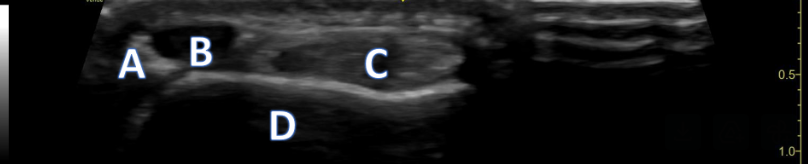

A 21-year-old female presents to the emergency room after falling from dancing on a table and injuring her right ankle. She is in severe pain and unable to bear weight comfortably with swelling and tenderness along the lateral malleolus. X-rays are taken and shown above.